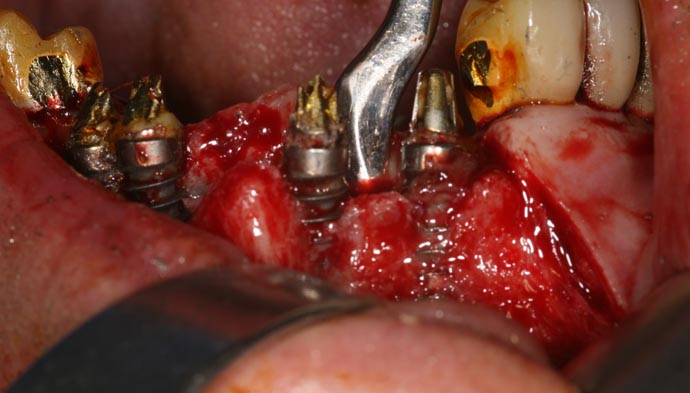

Cela s’est aggravé rapidement avec des infections et écoulements de pus. Après examen et radiographie panoramique, il est apparu que la majorité de mes implants étaient « expulsés » par mon os maxillaire, que certains implants avaient provoqué des abcès et que l’on observait une « cratérisation » généralisée de ces implants avec apparition de spires.

- Il s’est avéré urgent

- de déposer ces implants, de procéder à un comblement osseux, à la pose de neuf implants six mois plus tard et encore trois mois après, à la pose d’un nouveau bridge céramique. Ces multiples opérations ont été réalisées par un chirurgien-dentiste de Paris, suite à l’abandon de leurs responsabilités des »docteurs »précités.Les chirurgiens qui m’ont examinée mettent en cause le type d’implants posé, qui de par son architecture à larges spires induit une cratérisation systématique à court ou moyen terme.

25/11/2009 l’opération sur 7 implants défectueux on été remplacé (Trinon biomédical) retirés sur le mâchoire de la patiente remplacés par des implants Ankylos .

Infection prononcée sur tous les implants, 2 mois après les premières gènes qui allaient engendrer des abcès. et des gênes persistantes dans mon élocution. C’est le dentiste le responsable qui ma opéré ? quand l’os n’est pas suffisant sur le devant voilà le résultat! tout cela pour gagner de l’argent rapidement quelle honte.

Je garde de graves séquelles de tout cela. Ces multiples opérations ont été réalisées par un chirurgien-dentiste de Paris au courant de cette affaire qui m’a refait avec difficulté ce travail délicat à exécuter dépose des implants, suite à l’abandon de leurs responsabilités des »docteurs » J’ai subis multiples greffes osseuses, pose de nouveau implants Ankylos, puis des des prothèses et couronnes soit quinze interventions de février 2009 à mars 2010